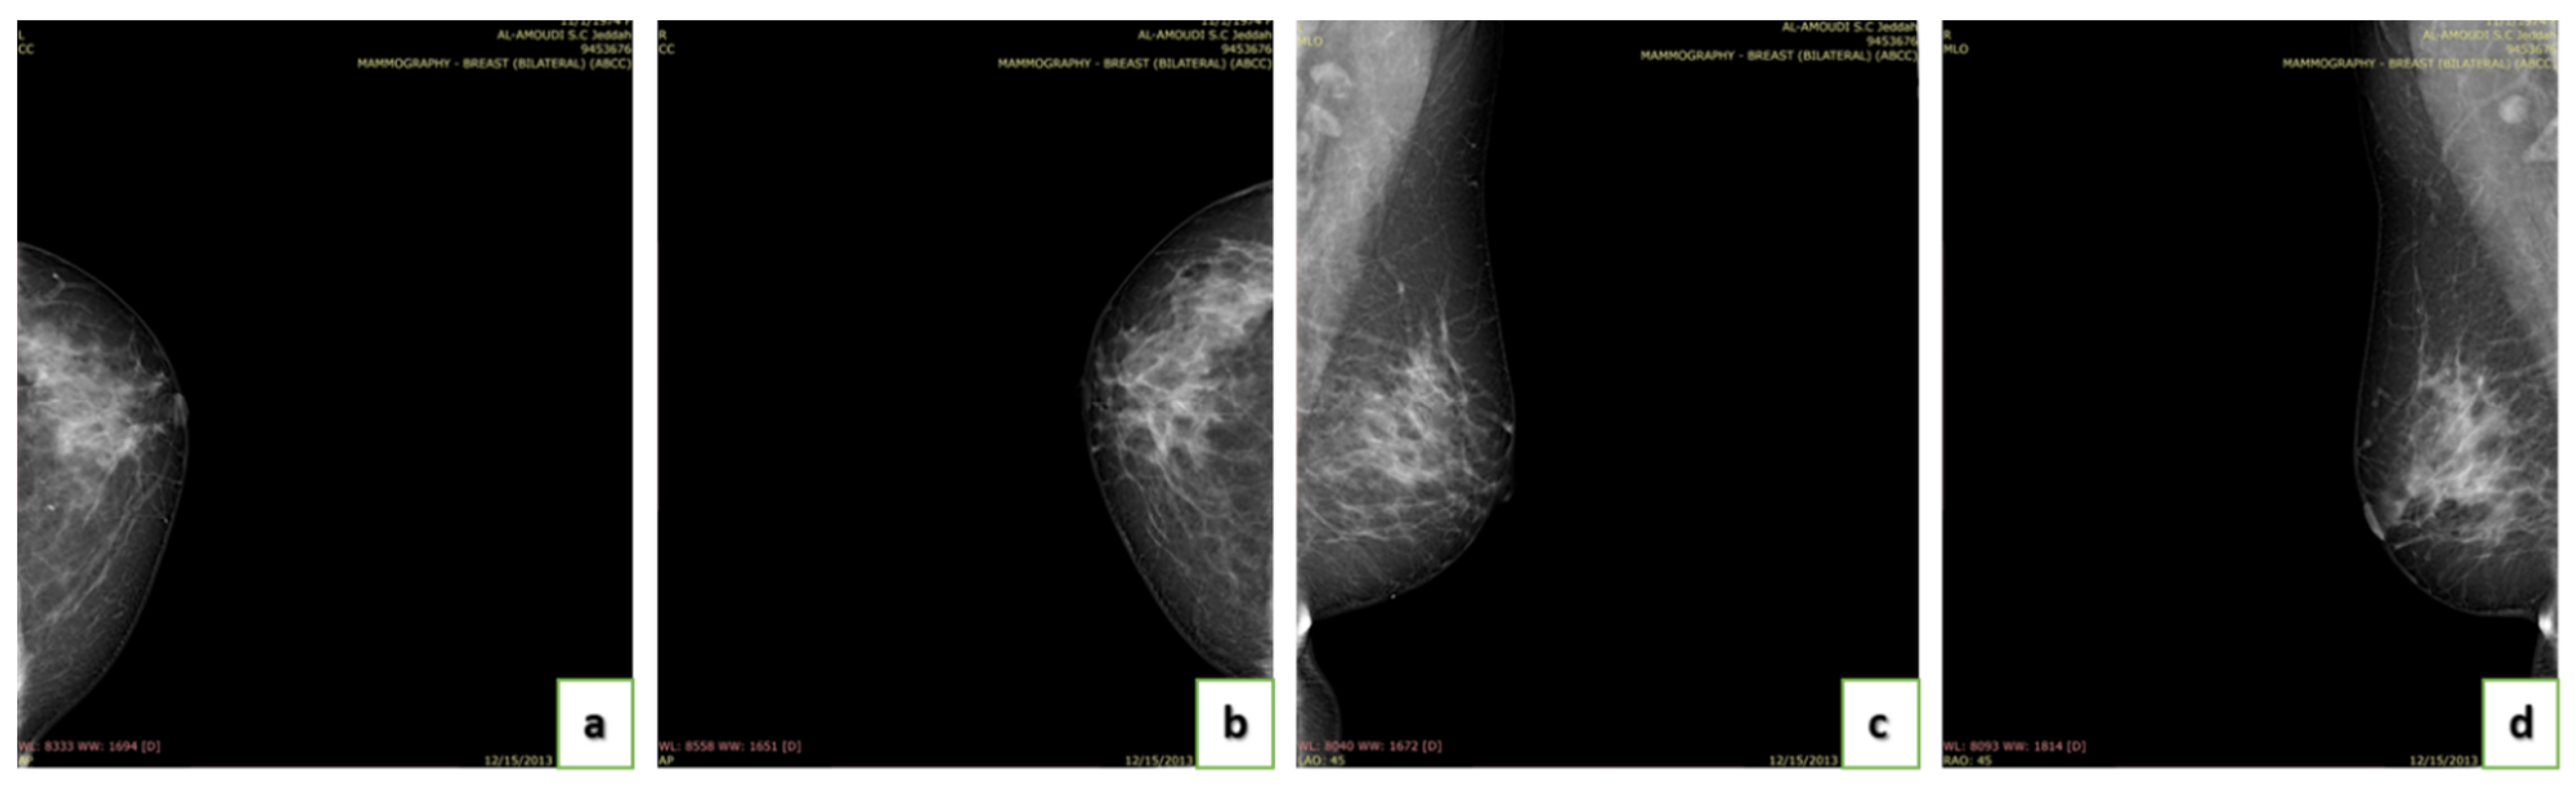

4.4. Breast Density

- A (0–25%): Almost entirely fatty indicates that the breasts are almost entirely composed of fat. One out of ten women has this result.

- B (25–50%): Scattered areas of fibroglandular density indicate some scattered areas of density, but most of the breast tissue is non-dense. Four out of ten women have this result.

- C (50–75%): Heterogeneously dense indicates that there are some areas of non-dense tissue but that most of the breast tissue is dense. Four out of ten women have this result.

- D (75–100%): Extremely dense indicates that nearly all breast tissue is dense. One out of each women has this result.